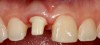

Plugging into digital workflows provides opportunities to integrate CAD/CAM technologies at every step of the treatment process for dental implants. In another example, a patient presented with a failing tooth No. 8 (Figure 6 and Figure 7). After discussing treatment options, the patient chose to forgo any treatment to address tooth and soft-tissue asymmetries and wanted to proceed with a dental implant-supported restoration without additional treatment. After integrated 3-dimensional planning, the tooth was extracted, and then an implant and the final custom CAD/CAM abutment (titanium base with zirconia supra-structure) were placed with a provisional restoration in the same visit (Figure 8 and Figure 9). Soft-tissue grafting was also done at the same visit to address the deficient buccal tissue height on No. 8 (Figure 10). At 3 months, the patient presented for the final restoration, with excellent healing around the implant (Figure 11) and soft-tissue healing guided by the custom abutment (Figure 12).

Fig 8. Extraction site No. 8 after atraumatic removal of the tooth.

Figure 8